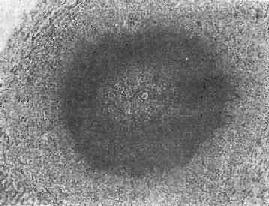

(1)急性虫卵结节:肉眼观为灰黄色、粟粒至绿豆大(0.5~4mm)的小结节。镜下见结节中央常有1~2个成熟虫卵,也偶可多达20个以上。这些成熟虫卵的卵壳上附有放射状嗜酸性的棒状体,也称为Hoeppli现象,用免疫荧光法已证实为抗原抗体复合物。虫卵周围是一片无结构的颗粒状坏死物质及大量嗜酸性粒细胞浸润。因其病变类似脓肿,故也称为嗜酸性脓肿(图19-5)。在坏死组织中可混杂多数菱形或多面形屈光性蛋白质晶体,即Charcot-Leyden结晶,系嗜酸性粒细胞的嗜酸性颗粒互相融合而成。随后虫卵周围产生肉芽组织层,其中有以嗜酸性粒细胞为主的炎症细胞浸润,还有单核巨噬细胞、淋巴细胞、浆细胞及少量中性粒细胞。随着病程的发展,肉芽组织层逐渐向虫卵结节中央生长,并出现围绕结节呈放射状排列的类上皮细胞层。类上皮细胞层逐渐加宽,嗜酸性粒细胞显著减少,构成晚期急性虫卵结节(图19-6),这是向慢性虫卵结节发展的过渡阶段。

图19-5 肝血吸虫病之急性虫卵结节

结节中心有一成熟虫卵,卵壳表面可见放射状物质,周围广泛坏死伴大量嗜酸性粒细胞浸润